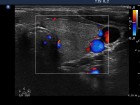

Ultrasonography: Both lobes were enlarged, moderately hypoechogenic, inhomogeneous and displayed increased vascularization.

2. Note the relation between volume, echogenicity, vascularization and hormone levels.